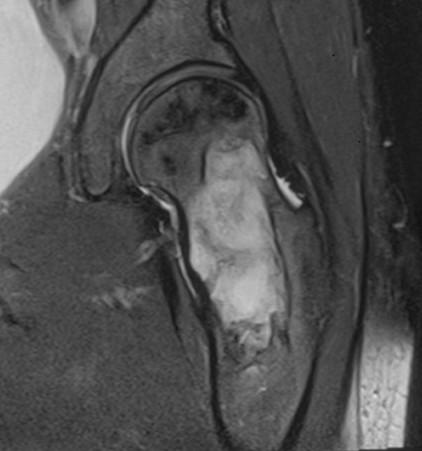

MRI

Low signal intensity T1 / High signal intensity T2